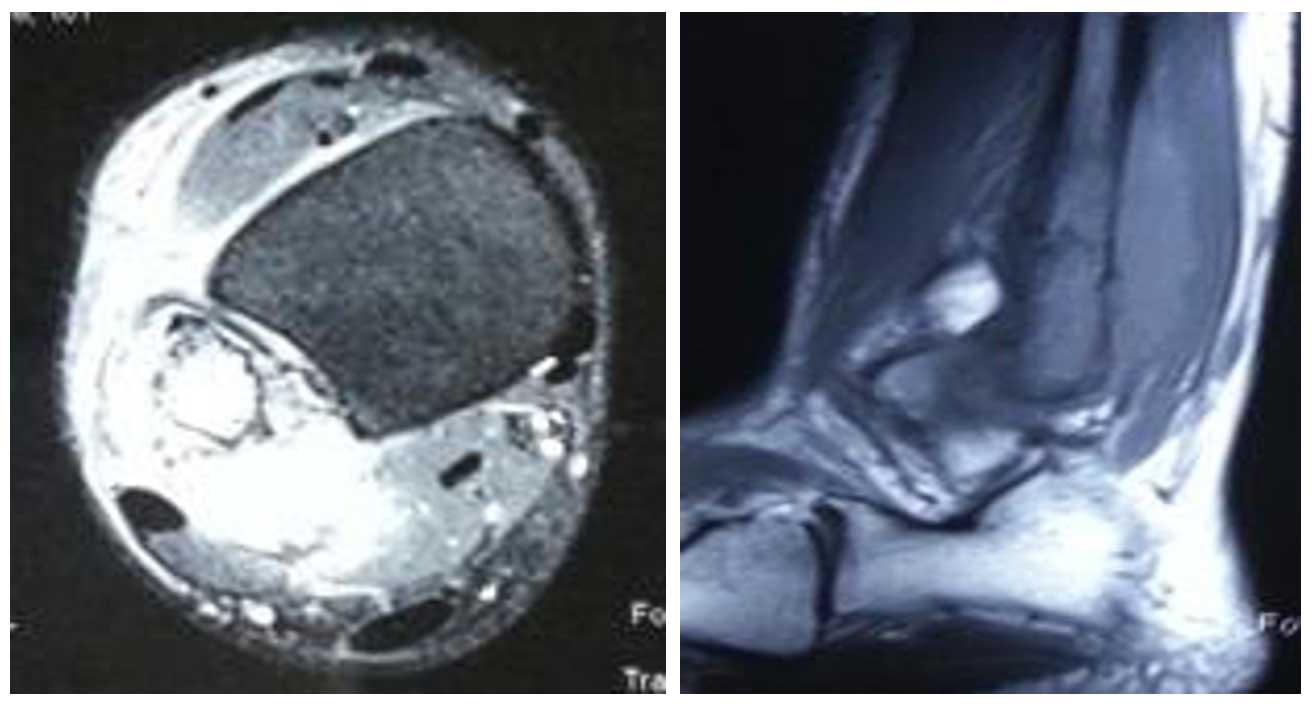

Ameliyat Öncesi: MR’da aynı lokalizasyonda çevreleyen yumuşak doku kitlesi ve ödem görülmekte.